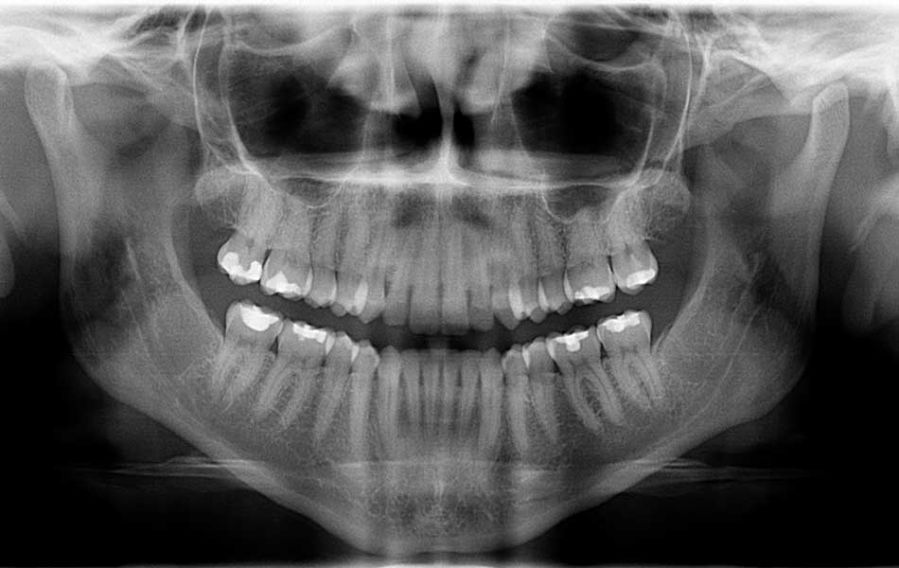

Odontoiatria Estetica

I trattamenti di odontoiatria estetica riguardano i denti sani e il loro aspetto estetico per quanto riguarda la forma, il colore e l'allineamento. Tra i trattamenti di odontoiatria estetica ci sono: